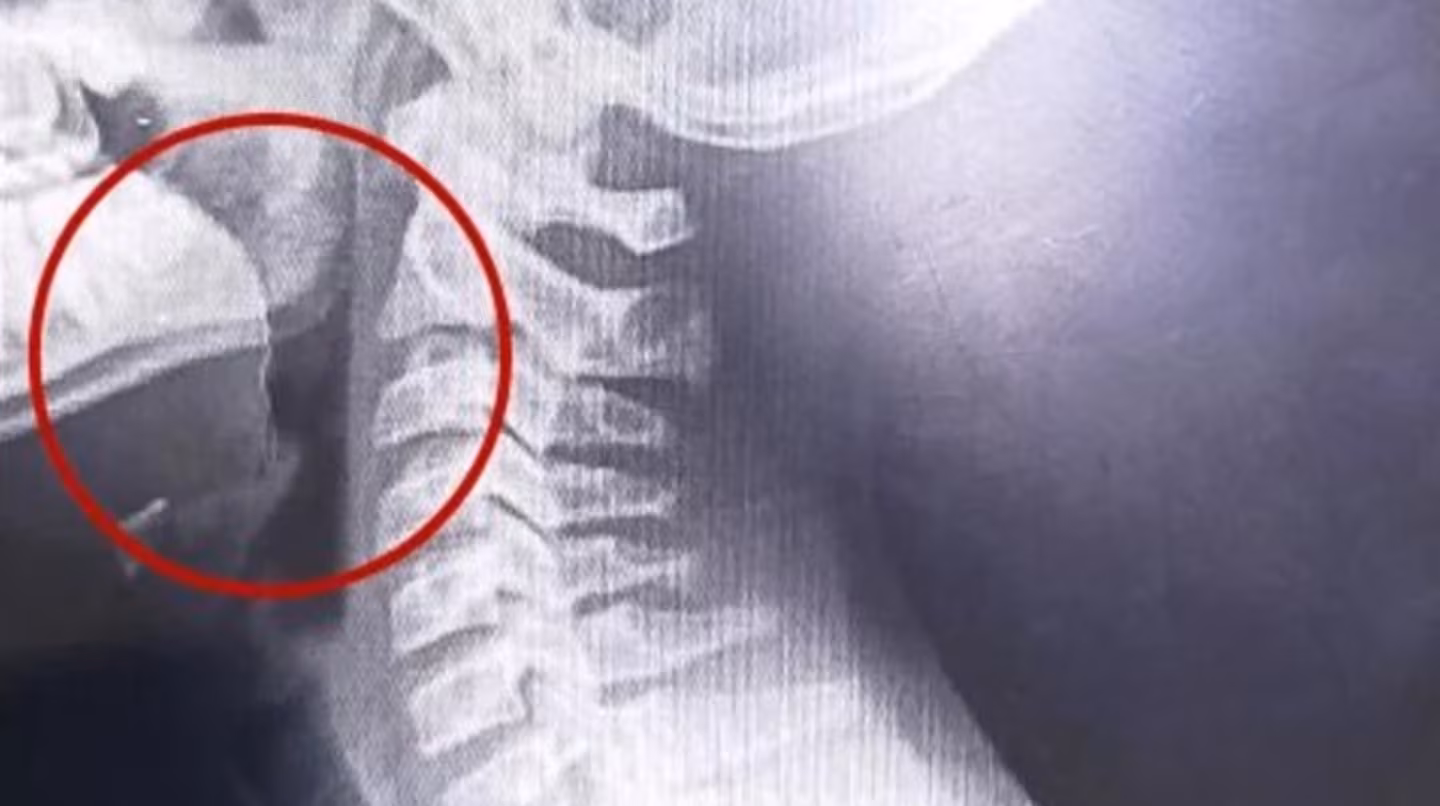

En el establecimiento decidieron internarlo de inmediato, y tras una serie de estudios, las placas lograron detectar un elemento inusual en el tracto respiratorio superior. Con ese resultado, le realizaron una laringoscopía y descubrieron que se trataba de un alambre fino que se había incrustado en la garganta del adolescente.

Encontraron que tenía un alambre fino incrustado en la garganta